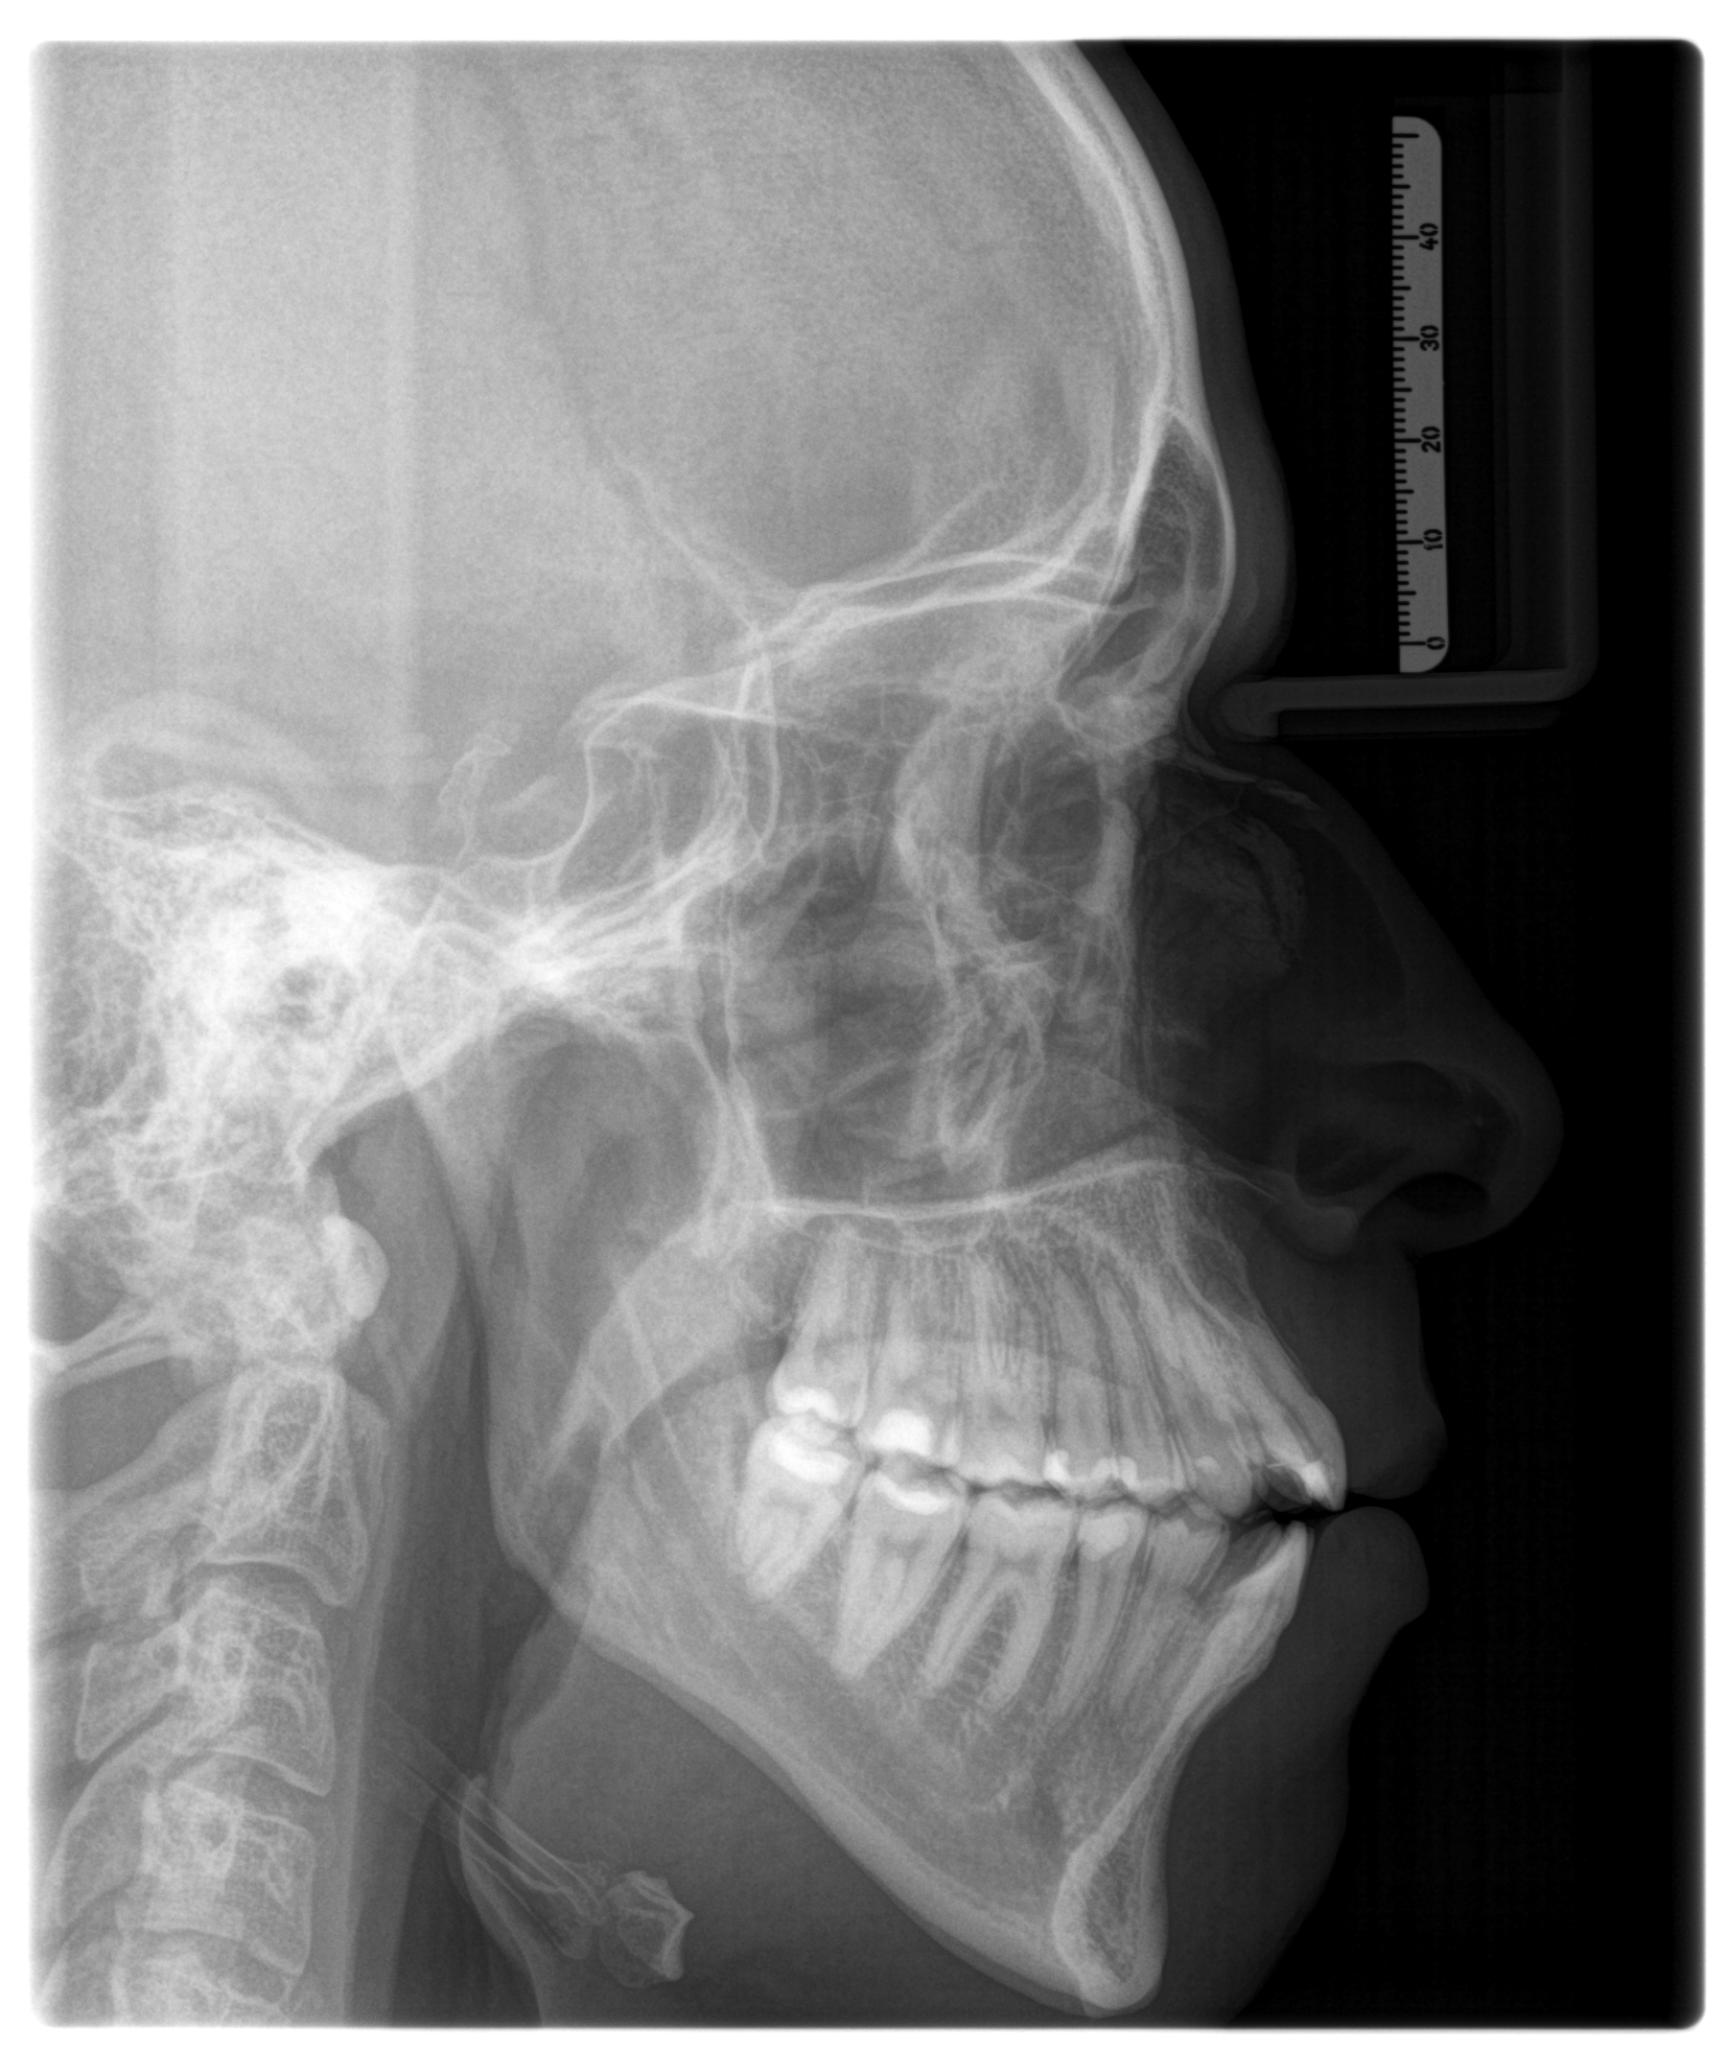

The plan is to expand (ideally with MSE) and then go for Bimax. Thoughts?

You mean that it will expand more one side than the other? I am a bit afraid of the famous MSE asymmetry to be honestyour palate is canted and mse will exacerbate this

yeah. You can get away with a little bit but if your goal is 12mm, the asymmetry will become obvious in your case.Y

I would like to expand between 6 and 8 mm, I do not wish to go crazy on the expansion. Some of the folks Ronald Ead's chats with have truly scary results, I may have to schedule a consultation with himyeah. You can get away with a little bit but if your goal is 12mm, the asymmetry will become obvious in your case.

Yes, I have a notorious compensation which I pretend to fix with corticotomy + invisalign after MSE. You are spot on, I did wear braces for years. The plan is to expand as much as possible and finish with surgery, although it may have never begun.I think you need ramus vertical osteotomy + bimax ccw. Did the surgeon mention bad teeth inclination? They seem very compensated (i assume you wore braces for a long time as a teenager). You would probably need to decompensate first and then have the surgery

I dont really know much about it, but your ramus seem short and that would make it bigger. The problem is that those are a lot of procedures which means a good chance of unfavourable outcome. Just make sure you explore this possibility with a good surgeonYes, I have a notorious compensation which I pretend to fix with corticotomy + invisalign after MSE. You are spot on, I did wear braces for years. The plan is to expand as much as possible and finish with surgery, although it may have never begun.

By the way, what would be the point of ramus vertical osteotomy?

I mean bimax + ramus lenghtening.The problem is that those are a lot of procedures which means a good chance of unfavourable outcome.